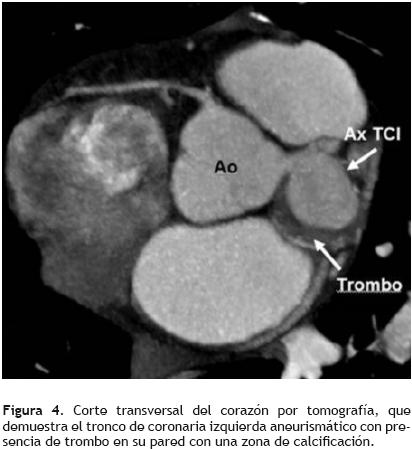

En abril del 2007, se valoró nuevamente con ecocardiograma transtorácico y transesofágico observándose el aneurisma del tronco de coronaria izquierda sin cambios con respecto a estudios previos (Figura 3). En una nueva valoración, aproximadamente un año después, se practicó una tomografía computarizada de control, en la cual no se observa crecimiento del aneurisma, así como tampoco se encuentran datos sugerentes de ruptura del mismo (Figura 4). Además, se realizó la evaluación del aneurisma de tronco con ecocardiograma tridimensional (Figura 5).